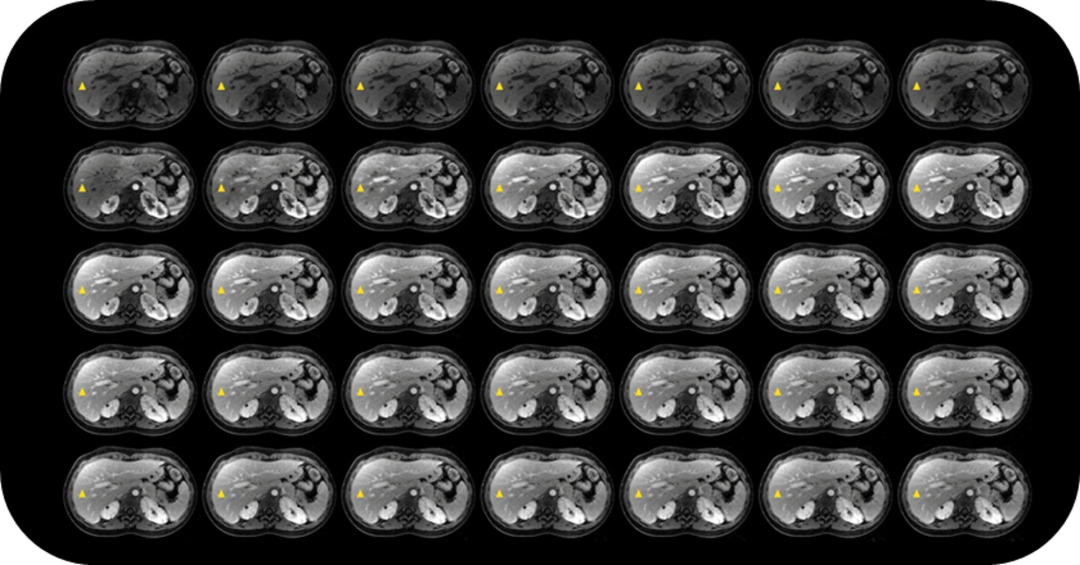

生命感知自由体部成像平台

MAGNETOM Vida磁共振系统可实现全新的生命感知自由体部成像:体部扫描时患者无需佩戴任何呼吸门控装置,全程自由呼吸就可完成扫描;在扫描过程中,Vida能根据病人的呼吸情况,实时控制磁共振信号采集;在BioMatrix生命矩阵系统的协助下,Vida可实现业界最快的动态增强成像——自由动态增强扫描,即:没有传统的增强期相,而是可以重建出指定的任意时间点的增强图像。

生命感知的自由动态增强

自由呼吸完成扫描,可冻结各个期相肝脏与腹壁运动